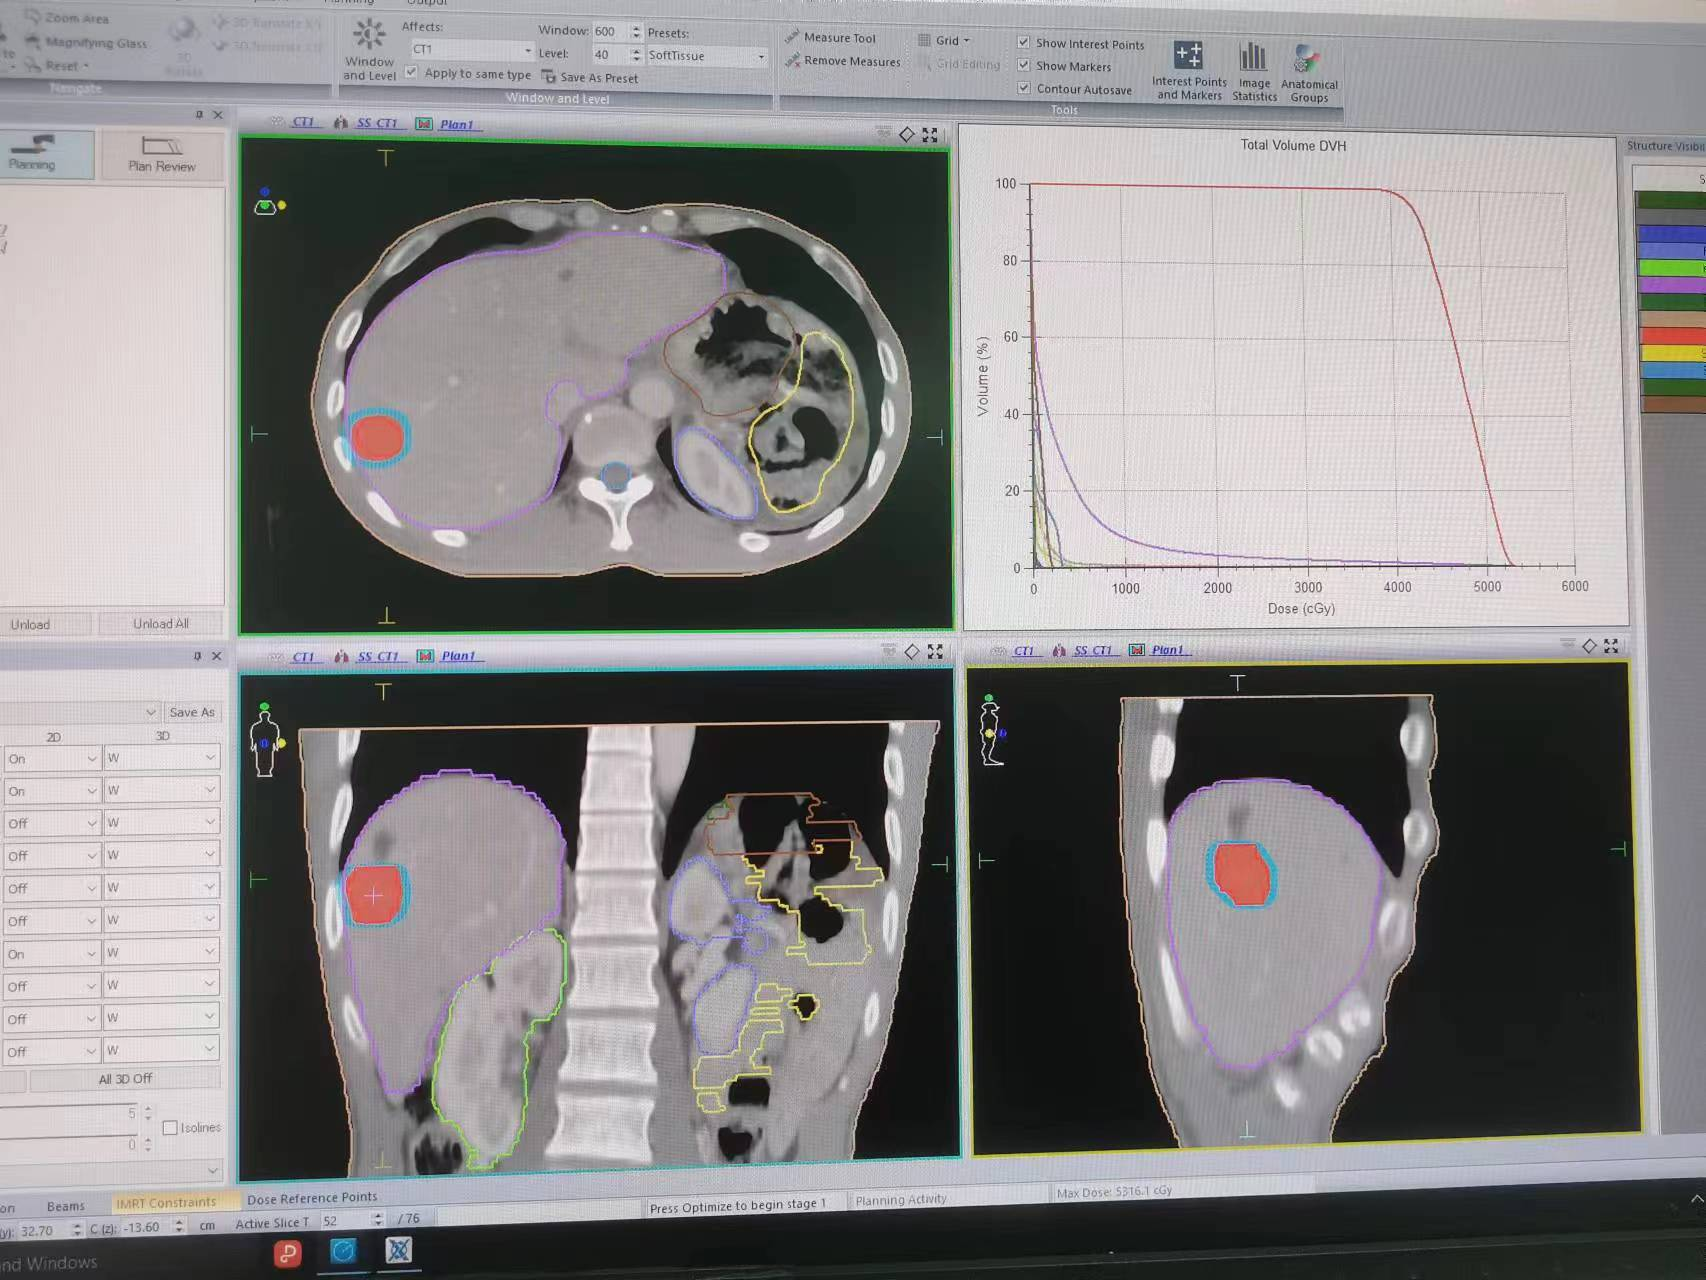

3. 将CT扫描得到的图像导入治疗计划系统,由医生勾画靶区及确定放射治疗方案。物理师制作放射治疗计划后经医师审核批准后传至治疗服务器待用。